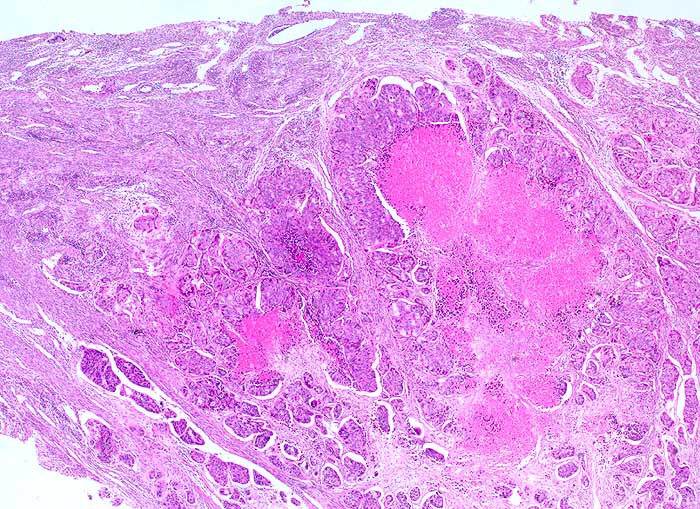

pit/ Zervixmetastase eines Kolonkarzinoms

Zervixmetastase eines Kolonkarzinoms

Eine für die Lokalisation atypische Morphologie eines Tumors sollte immer an die Möglichkeit einer Metastase denken lassen. Im Zweifelsfall lohnen sich eine Rückfrage beim Kliniker und das Studium aller Vorbefunde.